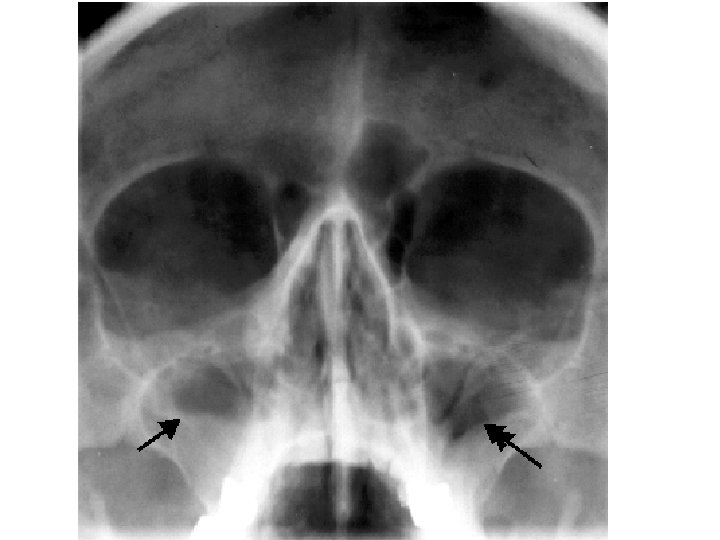

Maxillary sinus

Nasal meatus • Sphenoethmoidal recess: sphenoidal sinus • Sup. Meatus: post. Ethmoidal sinuses •

Nasal meatus • Sphenoethmoidal recess: sphenoidal sinus • Sup. Meatus: post. Ethmoidal sinuses • Middle meatus: -Bulla ethmoidalis← middle ethmoidal air sinuses Hiatus semilunaris← maxillary sinus, infundibulum Frontal sinus, ant. Ethmoidal air sinuses • Inf. Meatus ← nasolacrimal canal